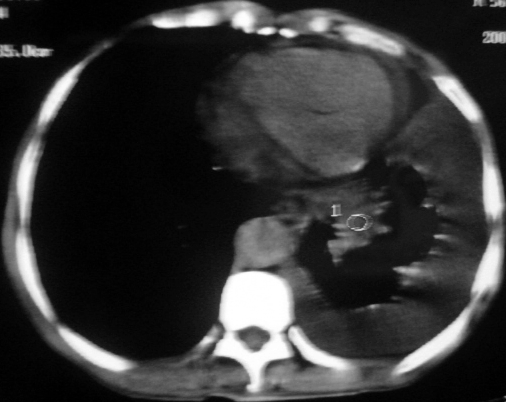

男,54岁,咳嗽,气喘半年,胸痛一月.

血性胸水

左侧胸腔积液 斜裂积液 心包积液 左肺不张 考虑左肺ca并胸膜心包转移。

支持左肺下叶中心型肺癌(累及舌叶)伴阻塞性肺炎、膨胀不全、胸腔积液、心包少量积液。

考虑左肺下叶中央型肺癌伴阻塞性肺炎及肺不张,纵隔受累可能,胸膜转移。